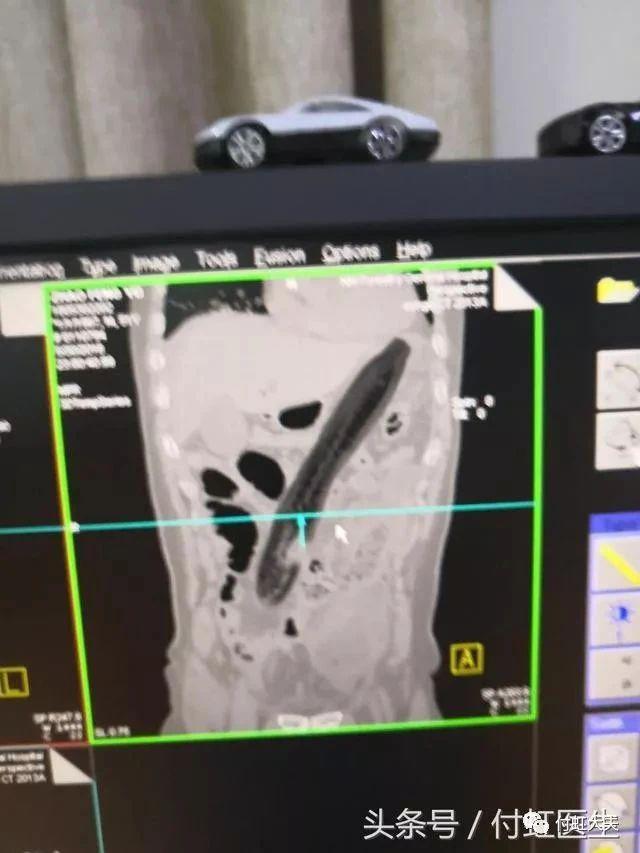

医生会通过一系列检查如直肠指诊、X 线来确定体内的异物是什么,在什么位置,这一点非常关键,因为只有搞清楚里面的真实情况,医生才能找到合适的方法把异物取出。